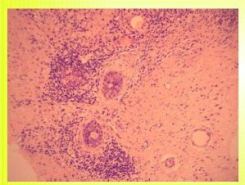

- CCB – core-cut biopsie: přítomnost granulomů, obrovských

mnohojaderných buněk, infiltrace leukocyty, plazmocyty a lymfocyty

v intra- a interlobulárním prostoru.

Histologie:

Ve vzorcích opakovaně nalezeny obrovskobuněčné granulomy se zánětlivým infiltrátem v okolí. Dále nalezena ztluštělá stěna duktů, tuková nekrosa.